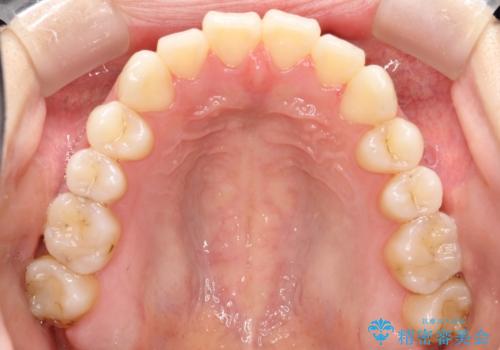

軽度の前歯のガタガタをインビザラインでの目立たない矯正

- 前歯のガタガタを主訴に来院されました。

軽度であったため、枚数制限のあるタイプのインビザラインのプランで治療することとしました。

軽度のガタガタを目立たずに手軽に矯正できるのもマウスピース矯正の魅力といえます。